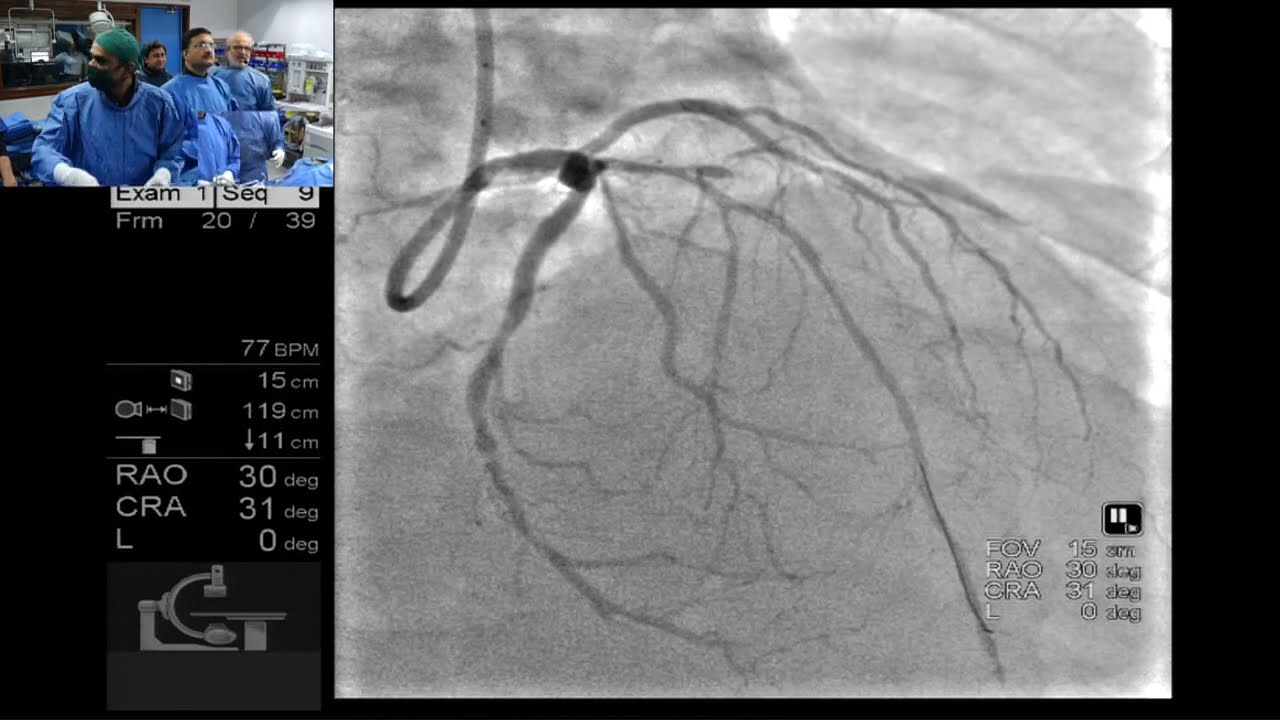

Описание: Сложный случай критического рестеноза внутри стента (ISR) в извилистой правой коронарной артерии (RCA), выполненный доктором Самиром Панчоли совместно с доктором Аманом Пателем. Использование Самиром ОКТ-изображений вызвало оживленную дискуссию о полезности ОКТ в интерпретации патофизиологии отказа стента. Увлекательные беседы между доктором Халедом Зиадой, Самиром Панчоли и участниками дискуссии в аудитории Нирма еще больше обогатили сессию.

Профессор доктор Самир Панчоли, MD, MSCAI, FAHA, FACC

Медицинский центр Администрации по делам ветеранов, Уилкс-Барре,

Медицинская школа Гейзингер Содружества, Пенсильвания, США